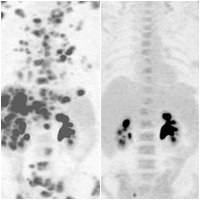

สหรัฐฯ ทดลองยารักษามะเร็งตัวใหม่ กำจัดเซลล์มะเร็งได้ไม่เหลือ